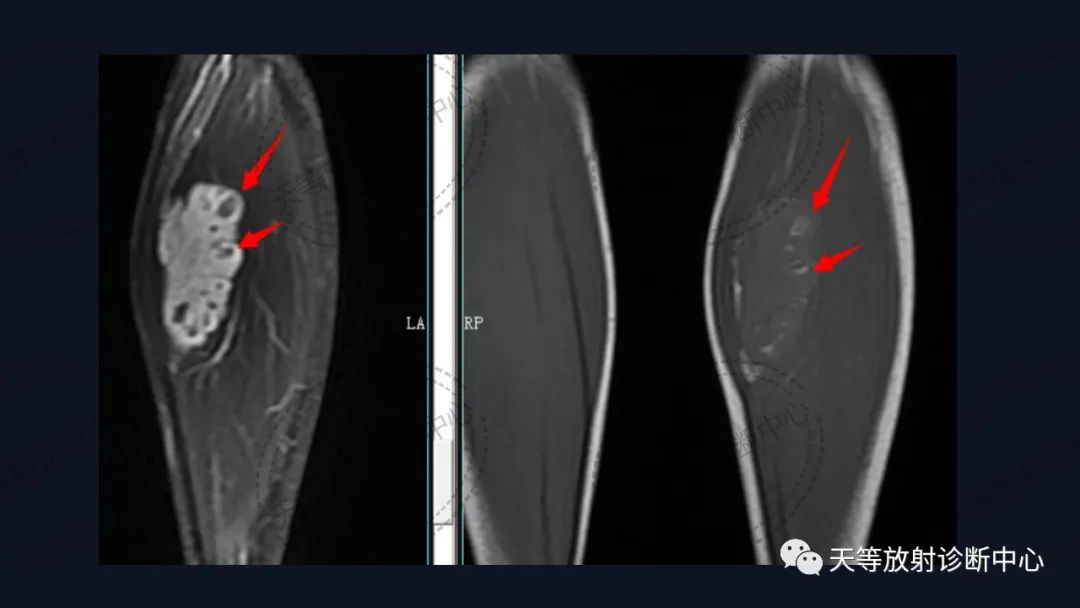

上图:DWI呈明显高信号影。

T1WI肿块边缘见环状高信号影,考虑出血信号。